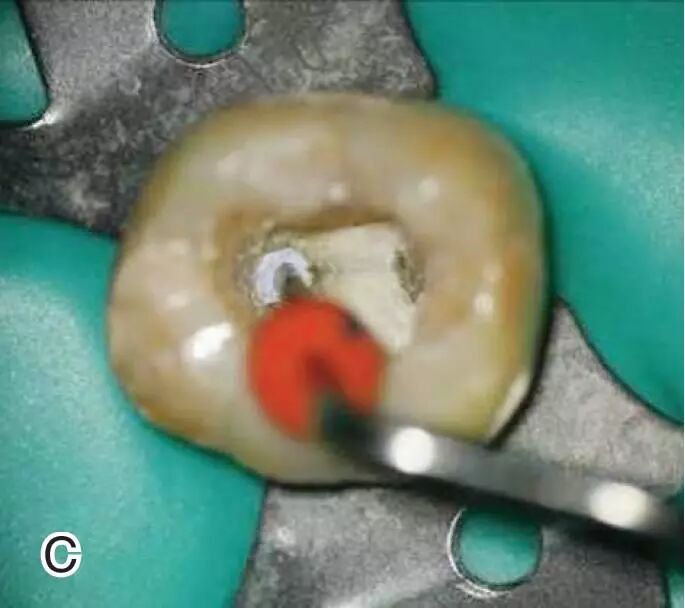

去除根管口外牙胶尖

调节好携热器的工作温度,将携热器工作尖放置在根管口,启动加热源,去除根管口外多余的牙胶尖部分,用大号的垂直加压器在根管口向根方轻轻加压。